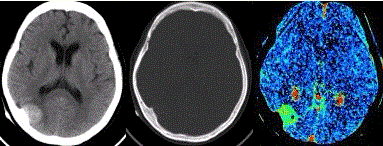

问题 患者女,60岁,头痛半月余。既往体健。腰椎穿刺检查提示脑脊液压力增高。CT及CT灌注表现如下图。 下列描述错误的是

选项 A.右侧枕部软组织肿块,边界清晰,邻近脑沟增宽 B.邻近骨质结构肥厚 C.病变内部可见钙化 D.CT灌注表面渗透图显示PS明显升高,提示新生血管内皮细胞不完整 E.CT灌注表面渗透图显示PS明显升高,提示病变无血-脑脊液屏障

答案 D